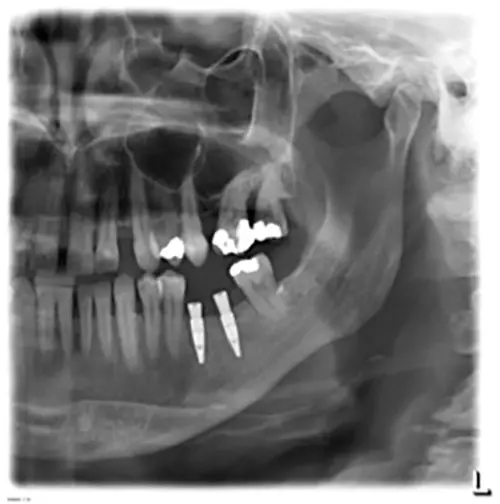

Eine 53-jährige gesunde Patientin stellte sich in unserer Klinik zur prothetischen Rehabilitation bei Vorliegen einer bilateralen Schaltlücke bei fehlenden Zähnen 37 und 36 vor. Zum Zeitpunkt der Erstvorstellung zeigte sich ein prothetisch und konservativ insuffizient versorgtes Gebiss mit einer Freiendsituation in regio 17 und 16 sowie Schaltlücken in den Regionen 37 und 36 sowie 46 und 47 (Abb. 1). Zur Beurteilung der radiologischen Ausgangssituation wurde präoperativ eine Digitale Volumentomographie angefertigt.